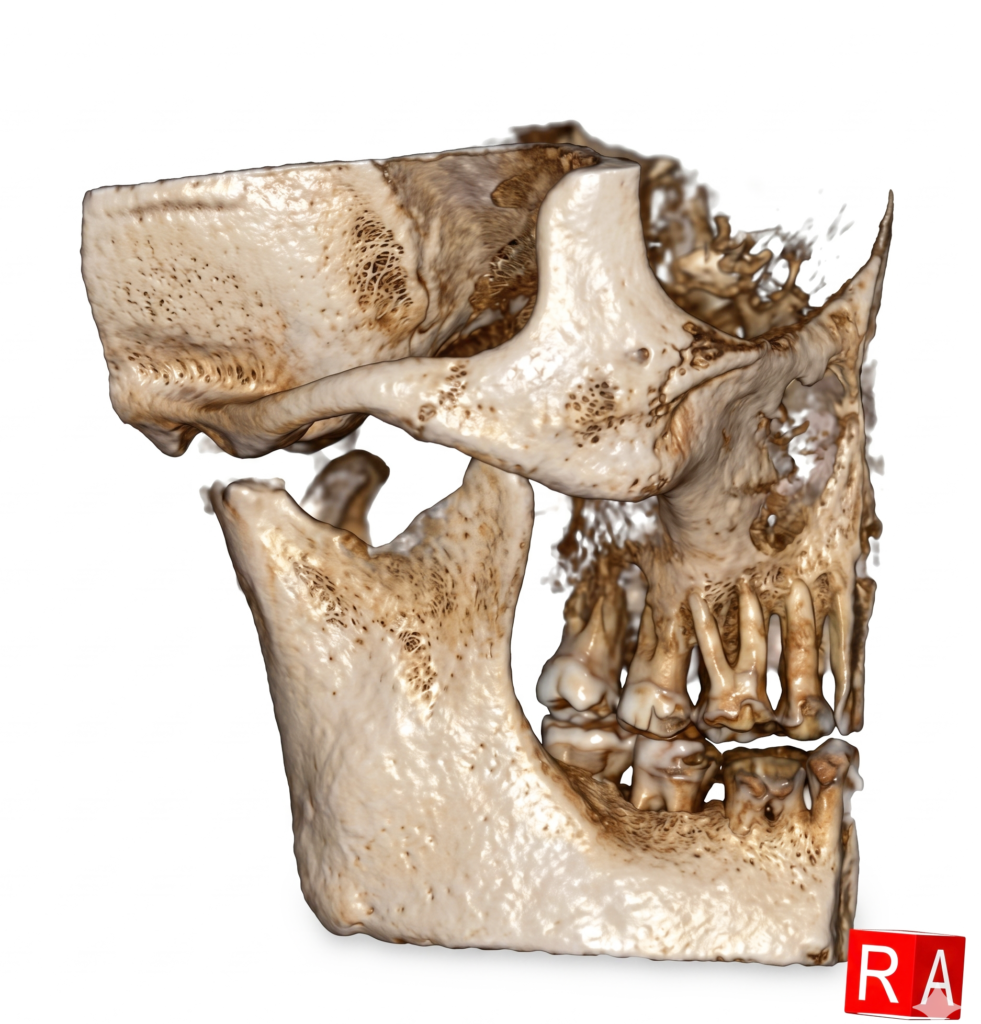

He is certified in Cone Beam Computed Tomography (CBCT) and has extensive experience in advanced radiological diagnosis. Dr. Singh is associated with several reputed centers across India as a consultant radiologist for CBCT reporting. His expertise includes implant planning, impacted teeth localization, oral and maxillofacial pathology interpretation, TMJ assessment, maxillary sinus evaluation, and airway analysis.